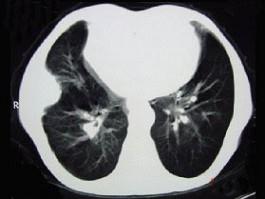

CT图像如下,最可能诊断为 ( )A、膈膨升B、纵隔肿块C、右侧胸膜良性病变D、肋骨病变侵犯胸壁E、右肺肺占位

问题 CT图像如下,最可能诊断为 ( )

选项 A、膈膨升 B、纵隔肿块 C、右侧胸膜良性病变 D、肋骨病变侵犯胸壁 E、右肺肺占位

答案 C